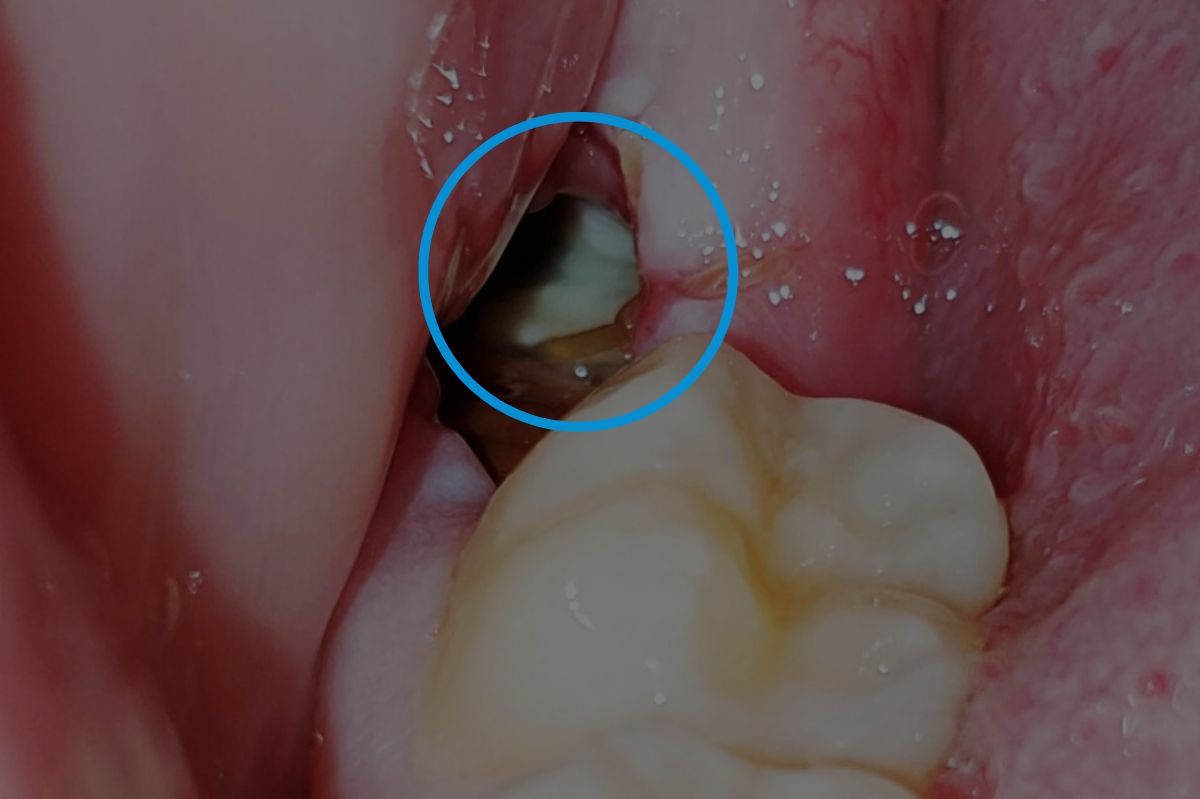

- Dry Sockets: A common issue where the blood clot becomes dislodged, exposing the bone. This leads to a dull ache around the third to fifth day after surgery. Treatment involves medicated dressings for pain relief and may require multiple visits to replace the dressing.